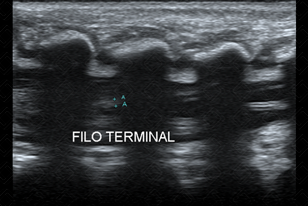

Texto alternativo para a imagem Figura 4. Créditos: Dra. Elazir Mota - Rio de Janeiro/RJ

Descrição da figura 4: Ultrassonografia de coluna lombossacra, do mesmo paciente, evidenciando o filum terminal – estrutura ecogênica que se estende o cone medular ao cóccix (A).

Algumas medidas devem ser analisadas durante o exame, como a altura do cone medula r (em geral, o cone medular deve estar ao nível de L2-L3. Nunca abaixo deste nível) e a espessura do filum terminal (sua espessura máximo encontra-se em torno de 0,18 a 0,2 cm).